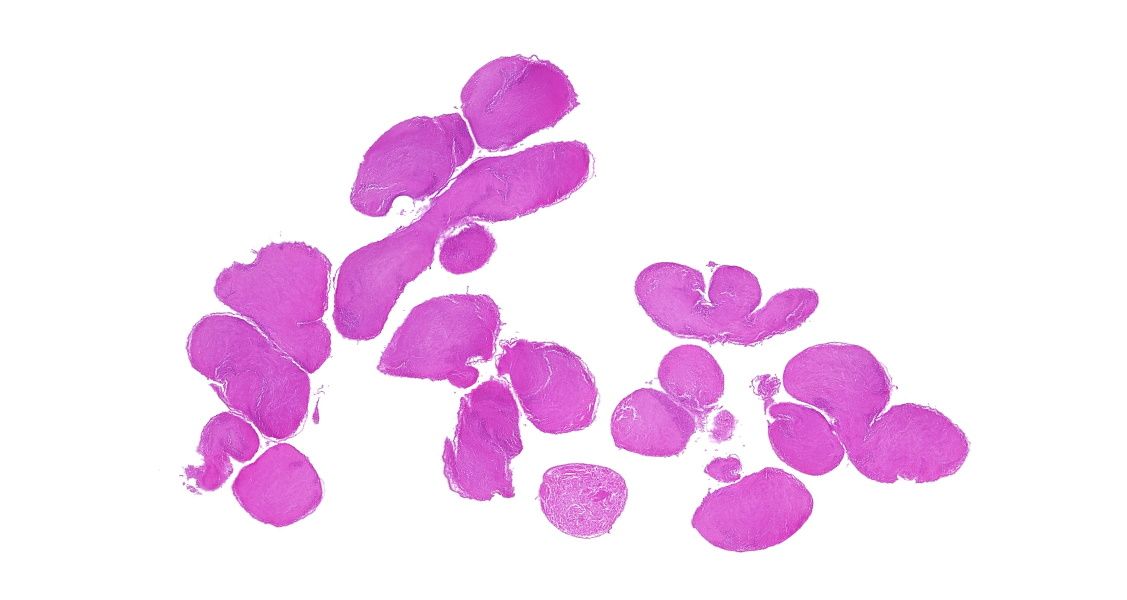

【技術(shù)原理】

蘇木精-伊紅染色法簡稱HE染色法,是最常用的染色方法。蘇木精(hematoxylin)是陽離子染料,能夠?qū)⒓毎藘?nèi)的嗜堿性物質(zhì)染成藍紫色。伊紅(eosin)是陰離子染料,能夠?qū)⒓毎|(zhì)和膠原纖維等染成粉紅色。

案例展示